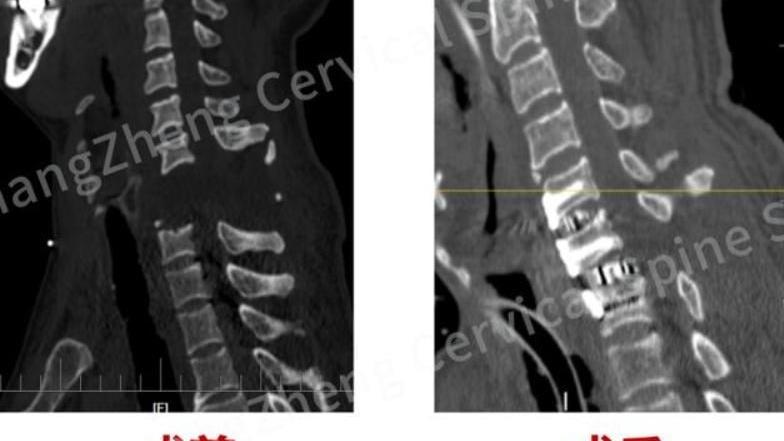

斷頸

手術前患者頸椎完全斷裂,十分駭人。(圖/翻攝《網易》)

上海傷者遭機械手臂打斷頸 「身首分離」獲醫生駁回